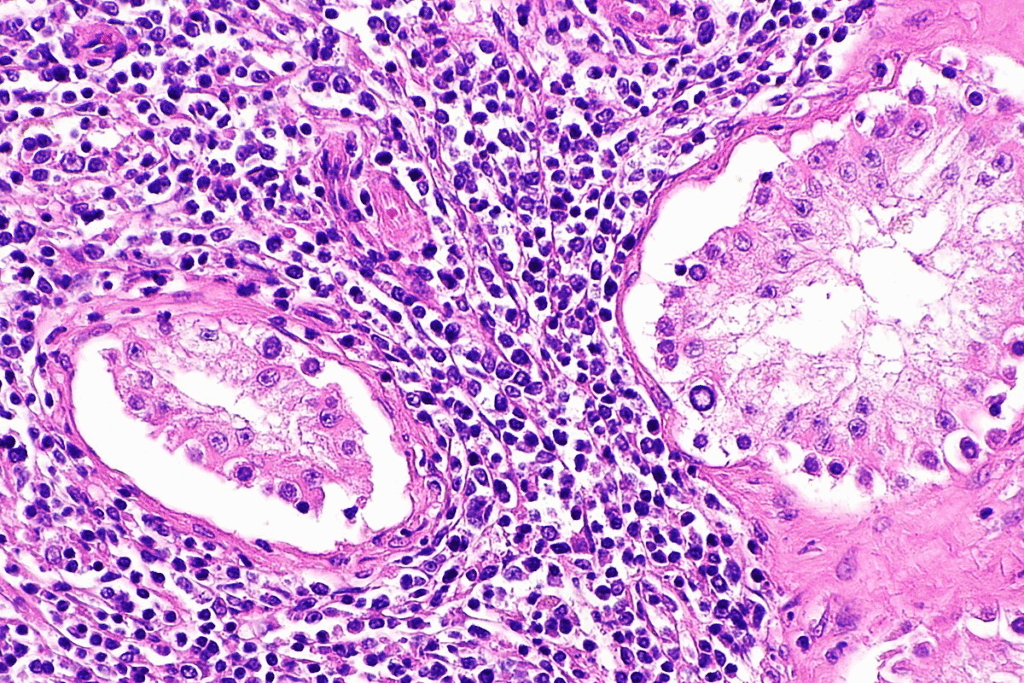

Lymphoma in kids is a cancer that starts in the lymphatic system, part of the immune system. It’s mainly divided into two types: Hodgkin lymphoma and non-Hodgkin lymphoma. Hodgkin lymphoma has Reed-Sternberg cells, while non-Hodgkin lymphoma doesn’t. Knowing these types helps doctors choose the right treatment and helps in epidemiological research.

Non-Hodgkin lymphoma (NHL) is more common in kids than Hodgkin lymphoma. It includes many types of lymphomas, each with its own treatment needs. The non-Hodgkin lymphoma rate in kids is high, with some types more common in certain ages. For example, Burkitt lymphoma is very common in young kids.

Burkitt Lymphoma and Rare Pediatric Lymphomas

Burkitt lymphoma is a fast-growing, aggressive NHL that affects kids more than adults. It grows quickly and has a high cell division rate. Other rare lymphomas in kids include lymphoblastic lymphoma and anaplastic large cell lymphoma. The Burkitt lymphoma incidence is very high in some areas, like equatorial Africa. Knowing about these rare types helps doctors find better treatments.